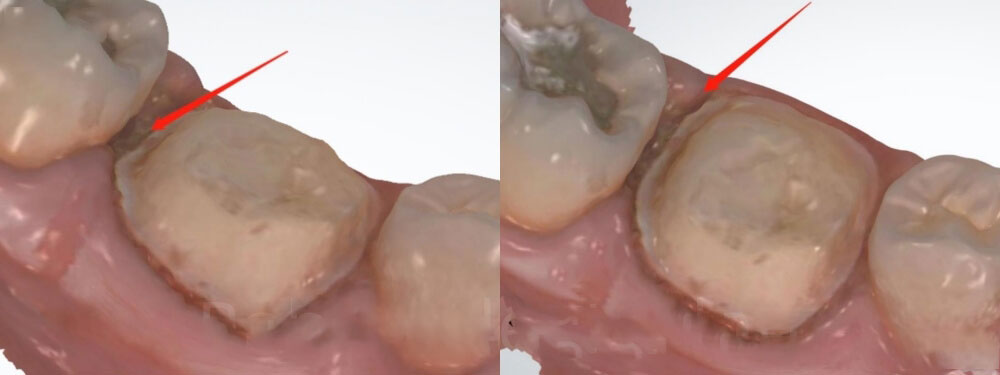

2. Checking the first-time digital scan

We can see that the first-time scan was with poor margin. The margins were covered a lot by the gum tissue. We could not clearly determine where the margin was. Therefore, we made this crown based on our experience. Please note that we normally try not to ask for new scans, because doctors are pretty busy. It is also troublesome for dentists to call back patients for new scans.

unclear margin for dental crown

3. Checking the new digital scan

Now let’s look at the new scan. The margin is very clear this time. The dentist cleaned blood and saliva. We believe the dentist used gum retraction cord before oral scanning. Now we can see that the distal margin of the new scan is a lot deeper than that of the first-time scan. This explains why the distal margin of the old crown was open.

Clear margin for dental crown